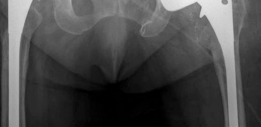

1. Radiographs: Standard AP pelvis, true lateral hip, and full-length femur radiographs are essential. These provide a baseline assessment of implant position, integrity, and preliminary evaluation of bone defects. Comparative views of the contralateral hip can aid in templating and understanding leg length discrepancy.

2. Computed Tomography (CT) Scan: A CT scan with metal artifact reduction sequence (MARS) is invaluable. It provides detailed, three-dimensional information regarding the extent and morphology of bone defects, aiding in precise Paprosky classification for both acetabulum and femur. It helps delineate cavitary versus segmental defects, assess column integrity, and identify areas of cortical fenestration or thinning. This information guides the selection of specific HPM augments, cones, or sleeves. ![Image](/media/upload/orthopedic-case-featured-125.png)